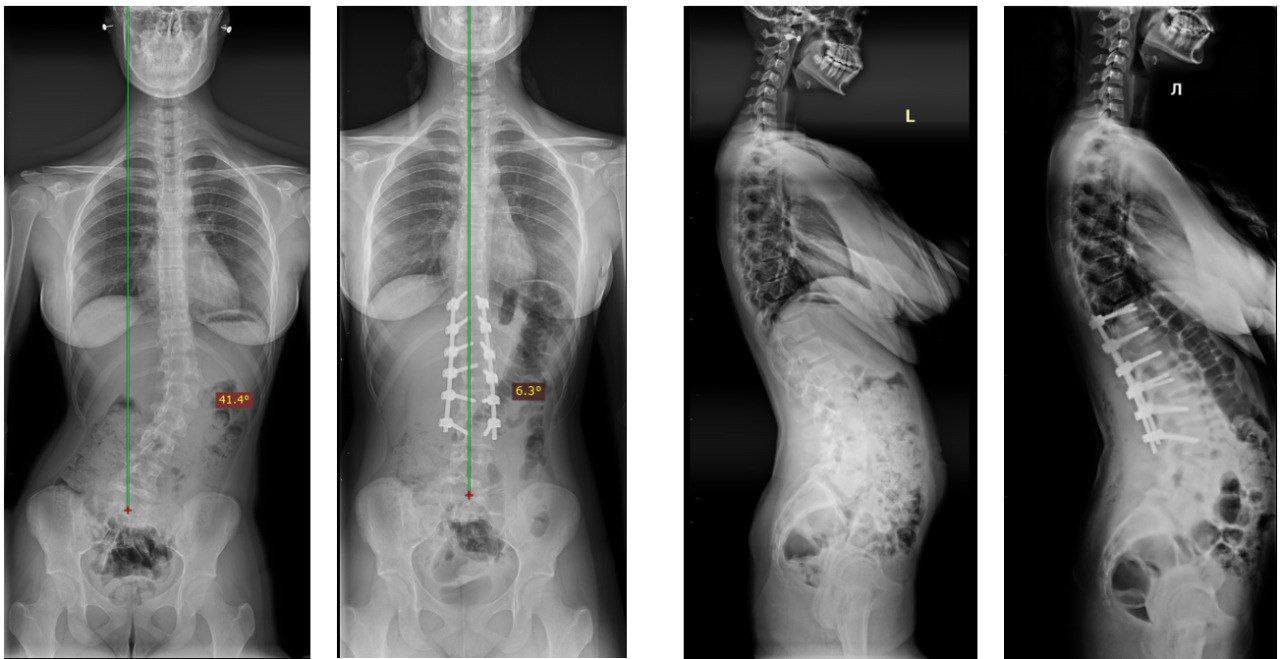

Система транспедикулярной фиксации "Sol" производства компании "Анатомика" позволила установить короткую конструкцию без потери эффективности фиксации. Благодаря уникальной апикальной деротационной технике, команда хирургов достигла отличной коррекции, значительно сократив количество опорных элементов.

Этот подход позволил не только исправить деформацию, но и максимально сохранить подвижность позвоночного сегмента, что крайне важно для качества жизни пациентки. По словам Александра Андреевича, пациентка чувствует себя хорошо, жалоб нет, и уже строит планы на будущее.